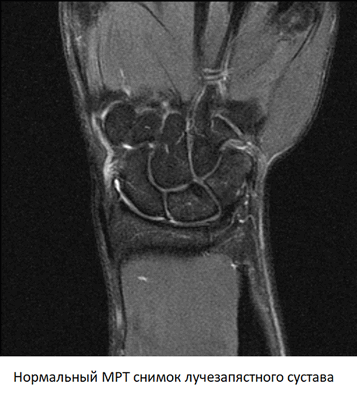

Снимки, полученные с помощью МРТ — это серия срезов толщиной от 1 мм, сделанная через область обследования в нескольких плоскостях. На них четко видны кости, образующие лучезапястный сустав, суставная полость и суставной хрящ, оболочка сочленения, связки, мышцы и их сухожилия.

При расшифровке снимков врач обращает внимание на ширину суставной щели, состояние хряща и суставной оболочки, целостность связочного аппарата. При наличии объемных образований МРТ позволяет с высокой точностью определить, что это — киста или опухоль. Изучая динамику накопления контраста, можно выявить ранние признаки воспаления или злокачественного процесса.